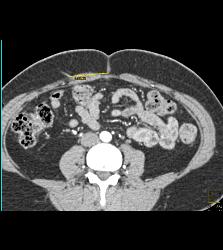

3D of Iliac Arteries